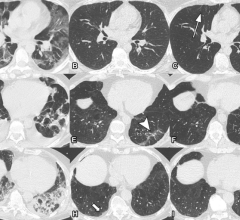

News | Coronavirus (COVID-19)

June 1, 2022 — According to ARRS’ American Journal of Roentgenology (AJR), evaluating chest CT findings offers an…

May 24, 2022 — A special type of MRI found lung abnormalities in patients who had previously had COVID-19, even those…